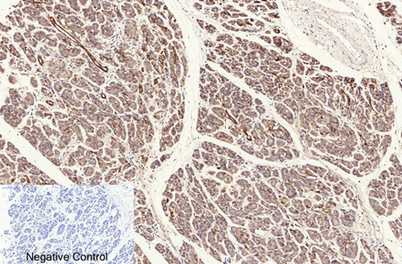

ÕŠ«õ┐ĪńöĄĶäæń½»ÕÆ©Ķ»ó

Õģ│µ│©ÕŠ«õ┐ĪÕģ¼õ╝ŚÕÅĘ

ÕŠ«õ┐Īµē½õĖƵē½Ķ┐×Õ┐ÖÕÆ©Ķ»ó

ÕŠ«õ┐Īµē½õĖƵē½Ķ┐×Õ┐ÖÕÆ©Ķ»ó